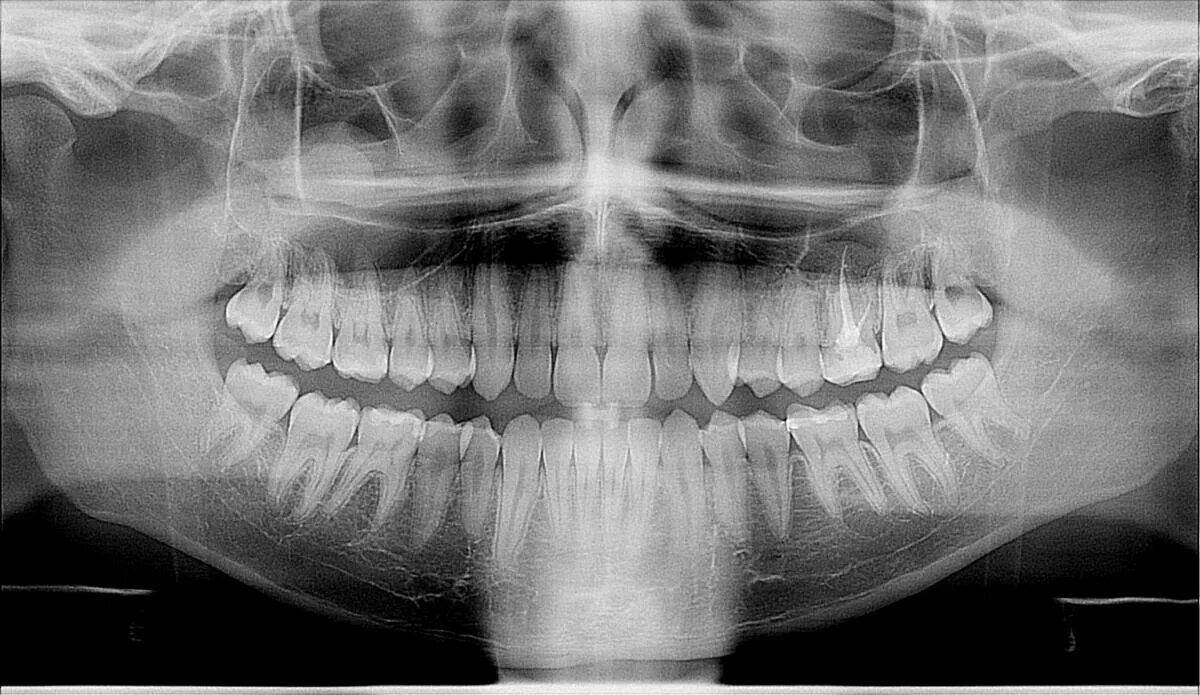

Киста зуба что это